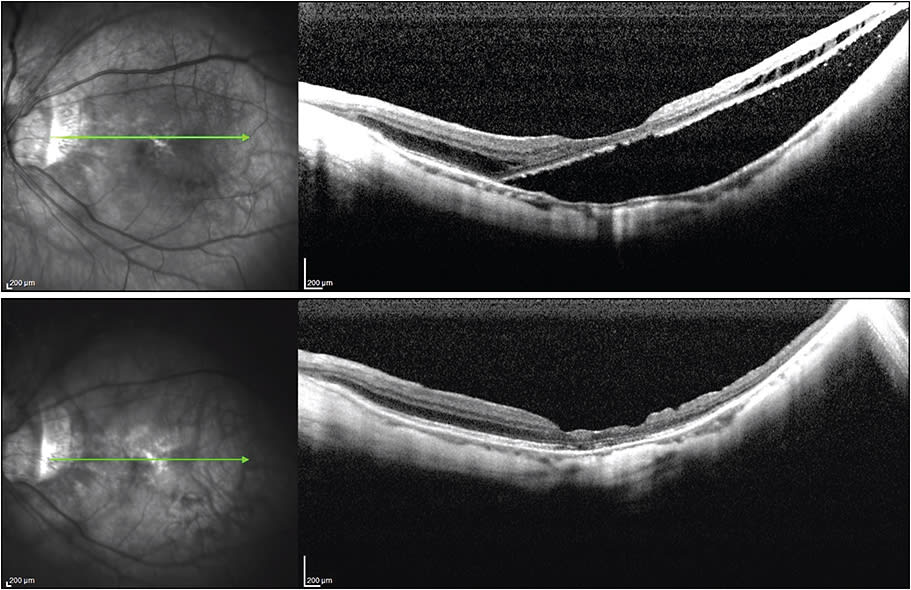

Figure 4. Pre- and postoperative OCT scans (at one week) in a case of a monocular individual with chronic schisis and detachment. The initial acuity was 20/80- and at six months it was 20/50-.

Figure 5. Pre- and postoperative OCT images of chronic macular schisis, tractional retinal detachment, and a lamellar macular break. The postoperative view is four months after the surgical intervention. Visual acuities were 20/60 preoperatively and 20/50 at four months. More settling of the detachment may still occur.

Figure 6. OCT image (top) of a case of residual detachment and schisis three years after a treatment by vitrectomy and ILM peel (visual acuity 6/400). On the bottom, the same macular region two weeks after placement of an augmented posterior-pole buckle. Nine months later, the visual acuity was 20/80.